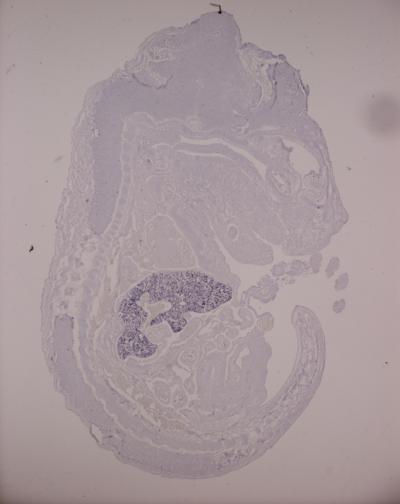

To form red blood cells, large, round cells known as precursors have to become small and disc-shaped, like balls of plasticine squeezed between finger and thumb. In the process, they must also produce the large quantities of haemoglobin that will allow them to transport oxygen, and shrink and dispose of their nucleus. The EMBL scientists found that two microRNAs, called MiR144 and MiR451, control the final stages of this process.

O'Carroll and colleagues genetically engineered mice to have no MiR144 or MiR451. They found that such mice had defects in the final stages of red blood cell formation, but produced red blood cell precursors not only in the bone marrow, but also in large quantities in the spleen. By increasing the number of precursors, the mice compensated for the fact that a smaller percentage of those precursors matured into functional red blood cells, and thus were able to survive with only a mild anaemia.